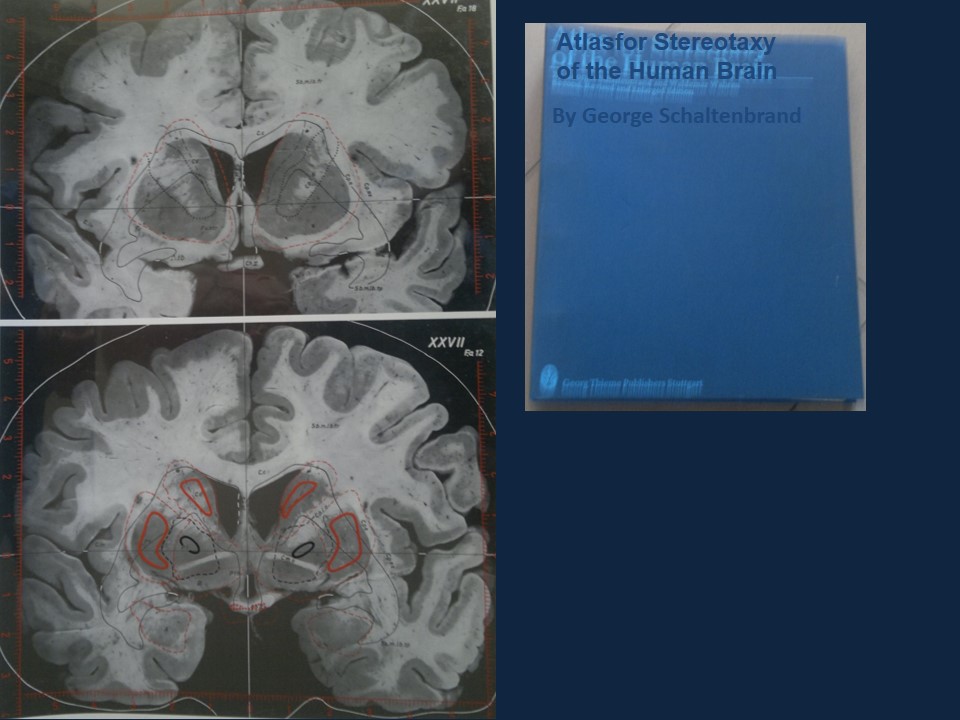

Metodología Estereotáctica o Estereotaxia

Dr. Guillermo Larrarte